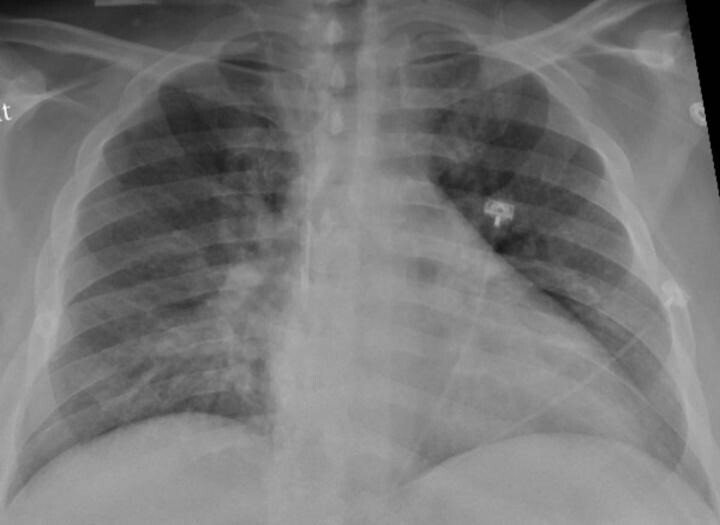

Un nuevo estudio del Colegio de Médicos y Cirujanos Vagelos de la Universidad de Columbia y del Centro Oncológico Integral Herbert Irving (Estados Unidos) ha dibujado la imagen más detallada hasta ahora de la infección por SARS-CoV-2 en el pulmón, revelando los mecanismos que dan lugar a la COVID-19 letal, y puede explicar las complicaciones a largo plazo y mostrar cómo la COVID-19 difiere de otras enfermedades infecciosas.

Publicado en la revista 'Nature', el estudio descubrió que, en los pacientes que murieron a causa de la infección, la COVID-19 desencadenó una trifecta perjudicial de inflamación desbocada, destrucción directa y regeneración alterada de las células pulmonares que intervienen en el intercambio de gases, y cicatrización pulmonar acelerada.

Este nuevo estudio es único con respecto a otras investigaciones, ya que examina directamente el tejido pulmonar (en lugar de esputo o lavados bronquiales) utilizando perfiles moleculares unicelulares que pueden identificar cada célula en una muestra de tejido y registrar la actividad de cada célula, lo que da lugar a un atlas de células en el pulmón tras la COVID-19.

El equipo examinó los pulmones de 19 individuos que murieron de COVID-19 y se sometieron a una autopsia rápida (a las pocas horas de la muerte), durante la cual se recogieron tejidos pulmonares y de otro tipo y se congelaron inmediatamente, y los pulmones de pacientes que no tenían COVID-19. En colaboración con investigadores de la Universidad de Cornell, los investigadores también compararon sus resultados con los pulmones de pacientes con otras enfermedades respiratorias.

En comparación con los pulmones normales, los pulmones de los pacientes con COVID-19 estaban llenos de células inmunitarias llamadas macrófagos, según el estudio. Normalmente, durante una infección, estas células mastican los patógenos pero también regulan la intensidad de la inflamación, lo que también ayuda en la lucha.

"En COVID-19, observamos la expansión y la activación incontrolada de los macrófagos, incluidos los macrófagos alveolares y los macrófagos derivados de los monocitos. Están completamente desequilibrados y permiten que la inflamación aumente sin control. Esto da lugar a un círculo vicioso en el que entran más células inmunitarias que causan aún más inflamación, lo que en última instancia daña el tejido pulmonar", destaca Izar.